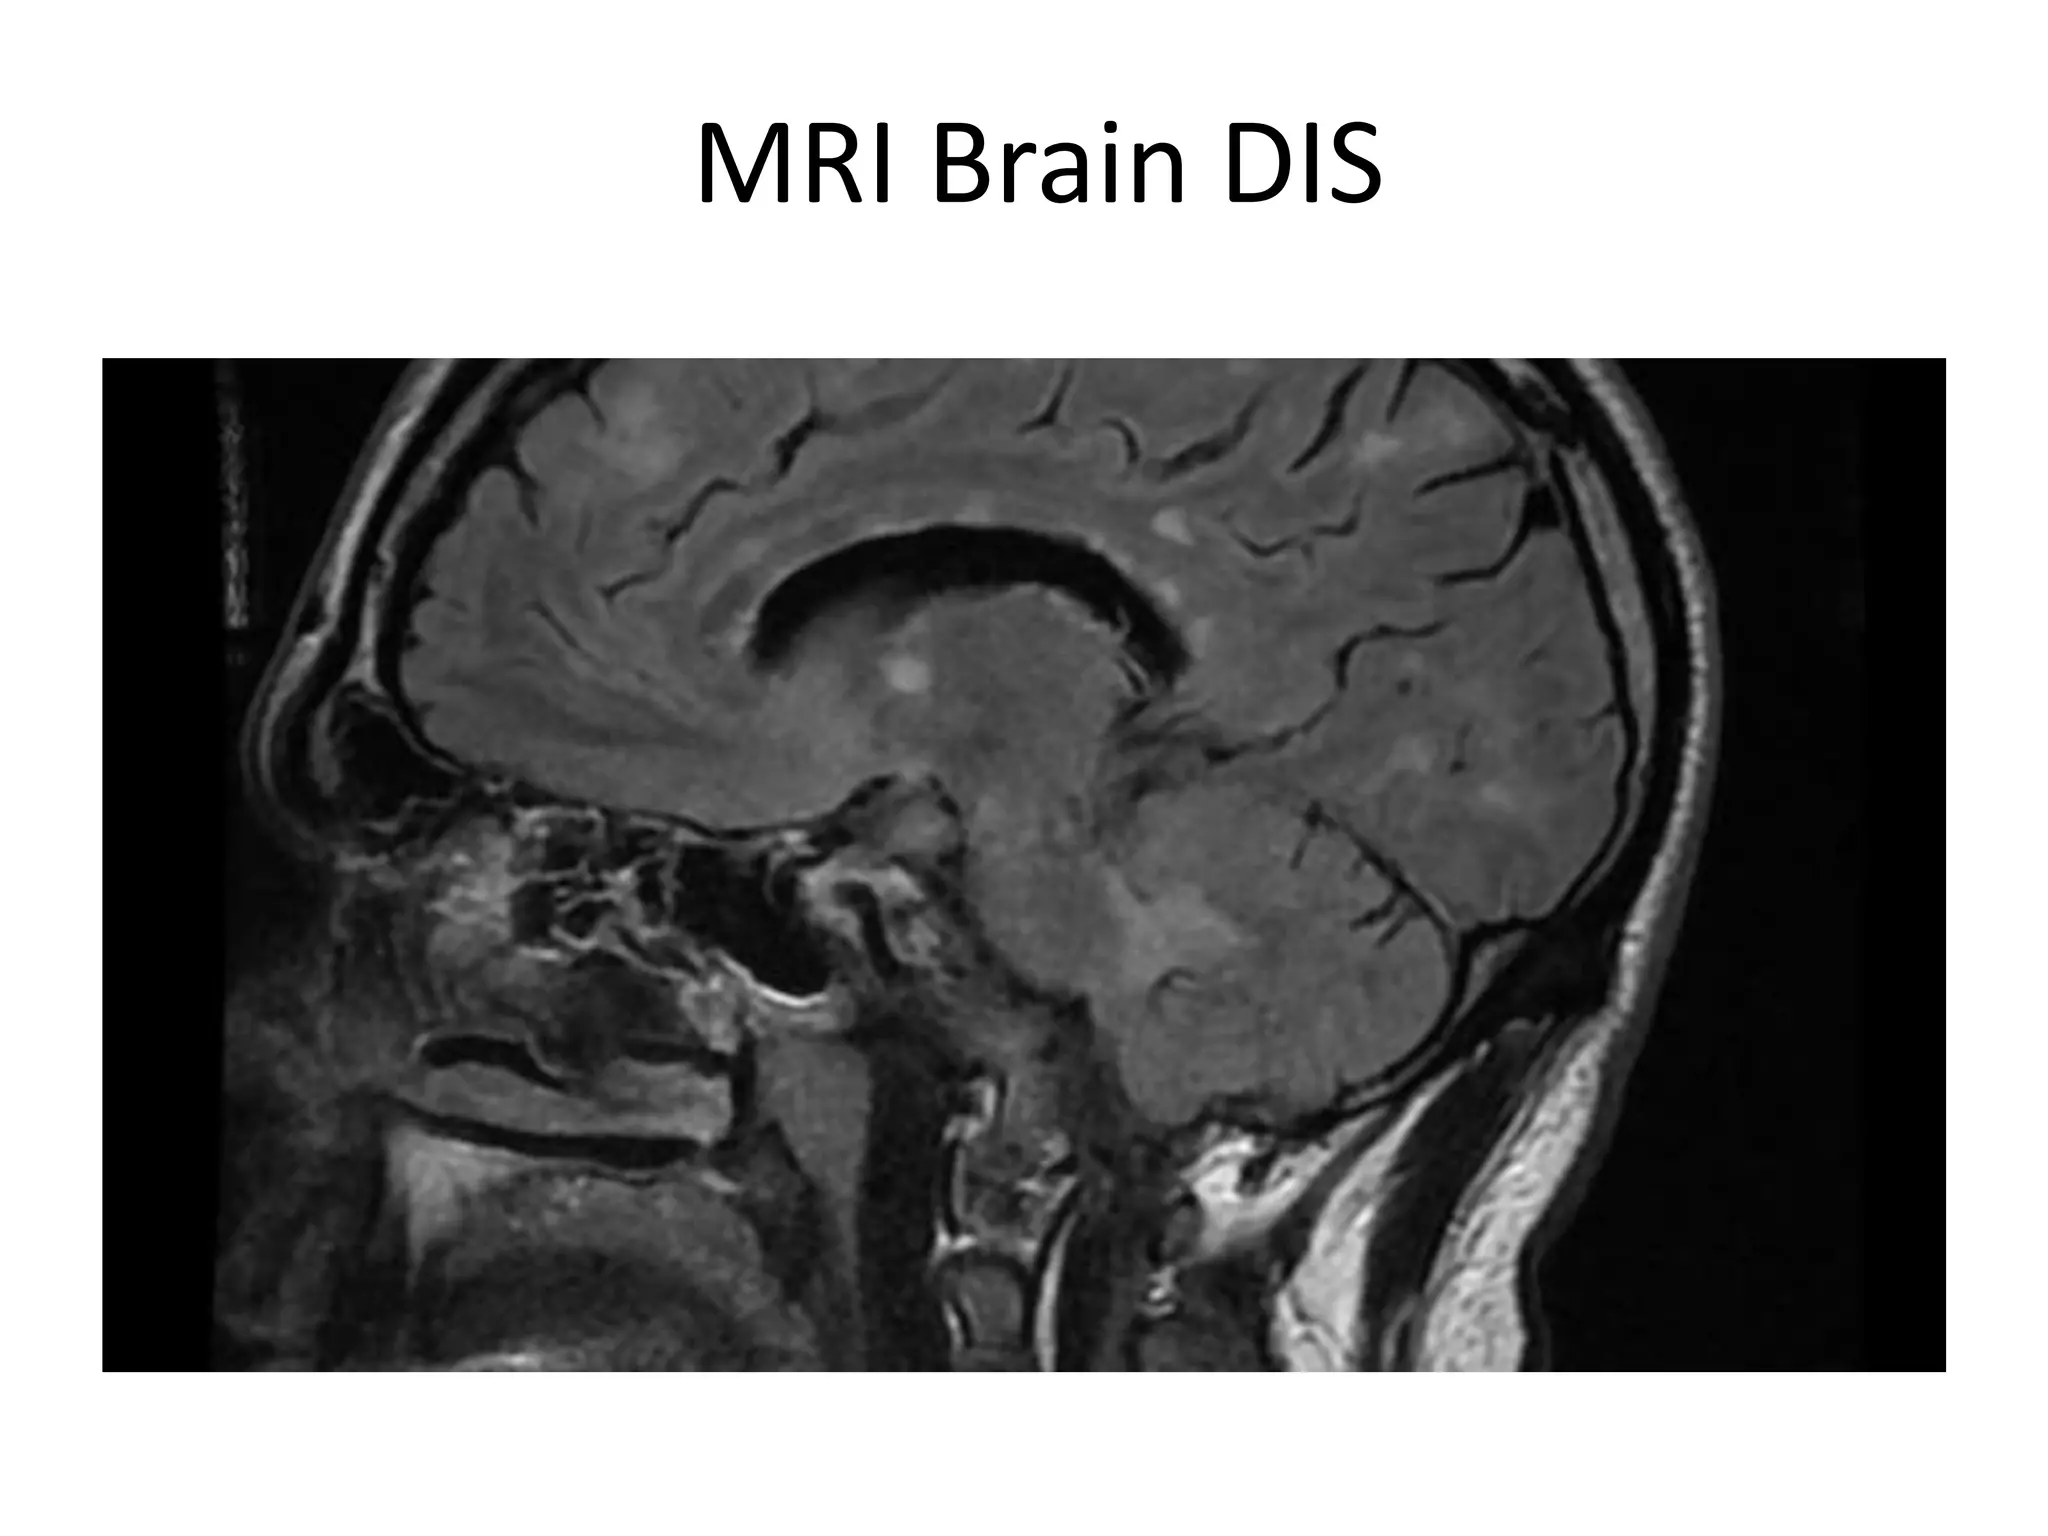

MRI Brain DIS

DIS demonstrated by 2 :

1- MRI brain

2. MRI cord

3. CSF oligoclonal bands

Dissemination in Space

Polman CH et al, Ann Neurol 2011; 69:292–302